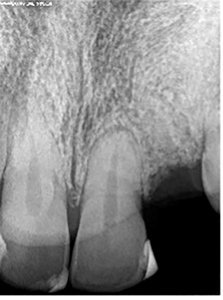

Pre-Treatment Assessment: indicated an extensively restored dentition, a stable periodontium with good healing of the 23-extraction site, adequate buccal (B), palatal (P), mesial (M) and distal (D) bone and adequate interocclusal clearance. The periapical radiograph showed good bone height and adequate interradicular distance between 22 and 24. (Figs. 1,2) After this initial assessment and discussion of treatment options, the patient elected to replace the missing 23 with an implant supported fixed restoration, the prognosis of which was assessed to be favorable. The surgical and prosthetic protocols were discussed, and informed consent was obtained after a discussion of treatment alternatives and cost. Impressions were made with Alginate material (Jeltrate® Chroma) using a stock tray and a surgical guide fabricated.

Fig. 1

Fig. 2